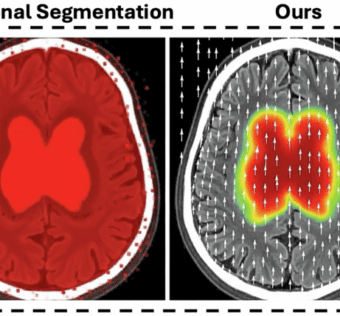

Modeling Ischemic Stroke Pathological Dynamics via Continuous Fields and Vector Flownpj Digital Medicine - (Thursday January 15, 2026) - Frequent Updates/ npj Digital Medicine | |

![]() | Precise localization of perfusion deficits in diffusion-weighted MRI (DWI) is critical for acute ischemic stroke management. However, existing deep learning methods typically produce discrete binary masks, failing to capture the continuous nature of ischemic... Exciting advancements in ischemic stroke analysis are here! The novel StrokeFlow framework transforms ischemic lesion representation from discrete segmentation masks to continuous fields, enhancing the accuracy and interpretability of stroke diagnostics. By integrating a scalar ischemic density field with a vector flow field, StrokeFlow captures the intricacies of ischemic injury, offering superior sensitivity and boundary accuracy. Evaluated on the ISLES 2022 dataset, it outperformed existing models, particularly in detecting small and multifocal lesions. This innovative approach promises a paradigm shift in clinical assessments of stroke, paving the way for improved patient outcomes.#HealthcareIT #AIinHealthcare #MedicalImaging #StrokeCare #DeepLearning #Neuroscience #DataScience As a healthcare IT expert, write a 100-word extractive summarization based on a blog post from the given text for posting on LinkedIn. The summary should capture key ideas from the entire post and its headings while staying focused, clear, and engaging. Use 5-7 relevant and popular online hashtags that are most likely to drive visibility and engagement. Avoid adding URLs or calls to action, and ensure the language is optimized for LinkedIn engagement style with a variable potential hook or attention-grabbing statement. The target audience is other healthcare IT professionals. Following is the title and text. { "id": "chatcmpl-CyMbq66jojK8bJ5CHtuFZ0acD1zH9", "object": "chat.completion", "created": 1768502626, "model": "gpt-4o-mini-2024-07-18", "choices": [ { "index": 0, "message": { "role": "assistant", "content": "Exciting advancements in ischemic stroke analysis are here! The novel StrokeFlow framework transforms ischemic lesion representation from discrete segmentation masks to continuous fields, enhancing the accuracy and interpretability of stroke diagnostics. By integrating a scalar ischemic density field with a vector flow field, StrokeFlow captures the intricacies of ischemic injury, offering superior sensitivity and boundary accuracy. Evaluated on the ISLES 2022 dataset, it outperformed existing models, particularly in detecting small and multifocal lesions. This innovative approach promises a paradigm shift in clinical assessments of stroke, paving the way for improved patient outcomes. nn#HealthcareIT #AIinHealthcare #MedicalImaging #StrokeCare #DeepLearning #Neuroscience #DataScience", "refusal": null, "annotations": [] }, "logprobs": null, "finish_reason": "stop" } ], "usage": { "prompt_tokens": 32831, "completion_tokens": 143, "total_tokens": 32974, "prompt_tokens_details": { "cached_tokens": 0, "audio_tokens": 0 }, "completion_tokens_details": { "reasoning_tokens": 0, "audio_tokens": 0, "accepted_prediction_tokens": 0, "rejected_prediction_tokens": 0 } }, "service_tier": "default", "system_fingerprint": "fp_29330a9688" } Prompt Tokens - 32831 |